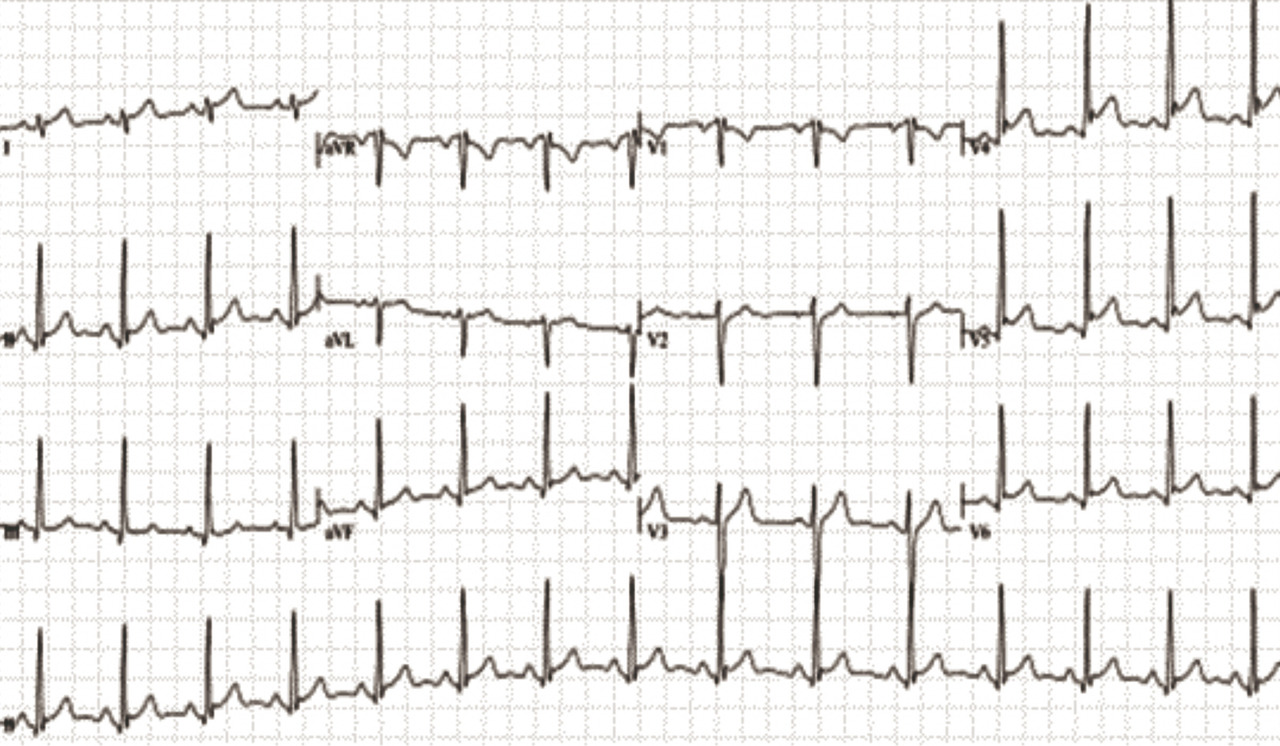

Électrocardiogramme

C’est souvent l’examen clé pour confirmer le diagnostic (fig. 1). On décrit classiquement une évolution selon quatre stades : 1) sous-décalage du segment PQ (souvent plus visible dans les dérivations inférieures DII, DII, aVF) et/ou sus-décalage du segment ST (diffus, convexe vers le haut, sans aspect de miroir) ; 2) normalisation du segment ST ; 3) négativation des ondes T sans sous-décalage du segment ST ; 4) normalisation de l’ECG. Il est toutefois rare d’observer ces quatre stades consécutivement, et les anomalies ECG ne sont présentes que dans 60 % des cas environ. L’ECG devra être répété pour mettre en évidence les anomalies décrites ci-dessus car les anomalies peuvent être fugaces.

La présence d’un microvoltage (QRS < 5 mm) est évocateur d’un épanchement péricardique significatif.